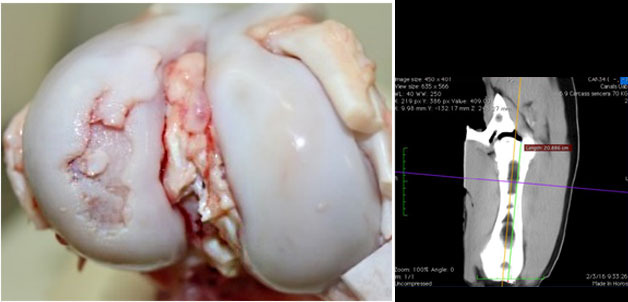

Visão macroscópica da articulação do joelho com lesão de osteocondrose grave no côndilo lateral do fêmur.

Visão de tomografia computadorizada da mesma lesão. Lesão grave de osteocondrose com ausência de ossificação na região subarticular do côndilo lateral do fêmur.